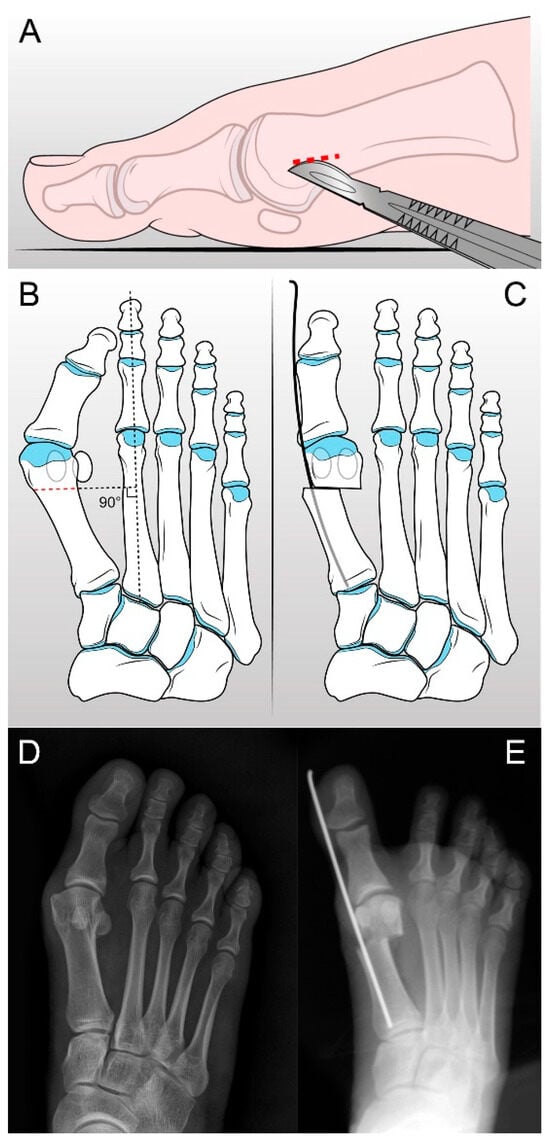

2.2. S.E.R.I. Operative Technique and Postoperative Management